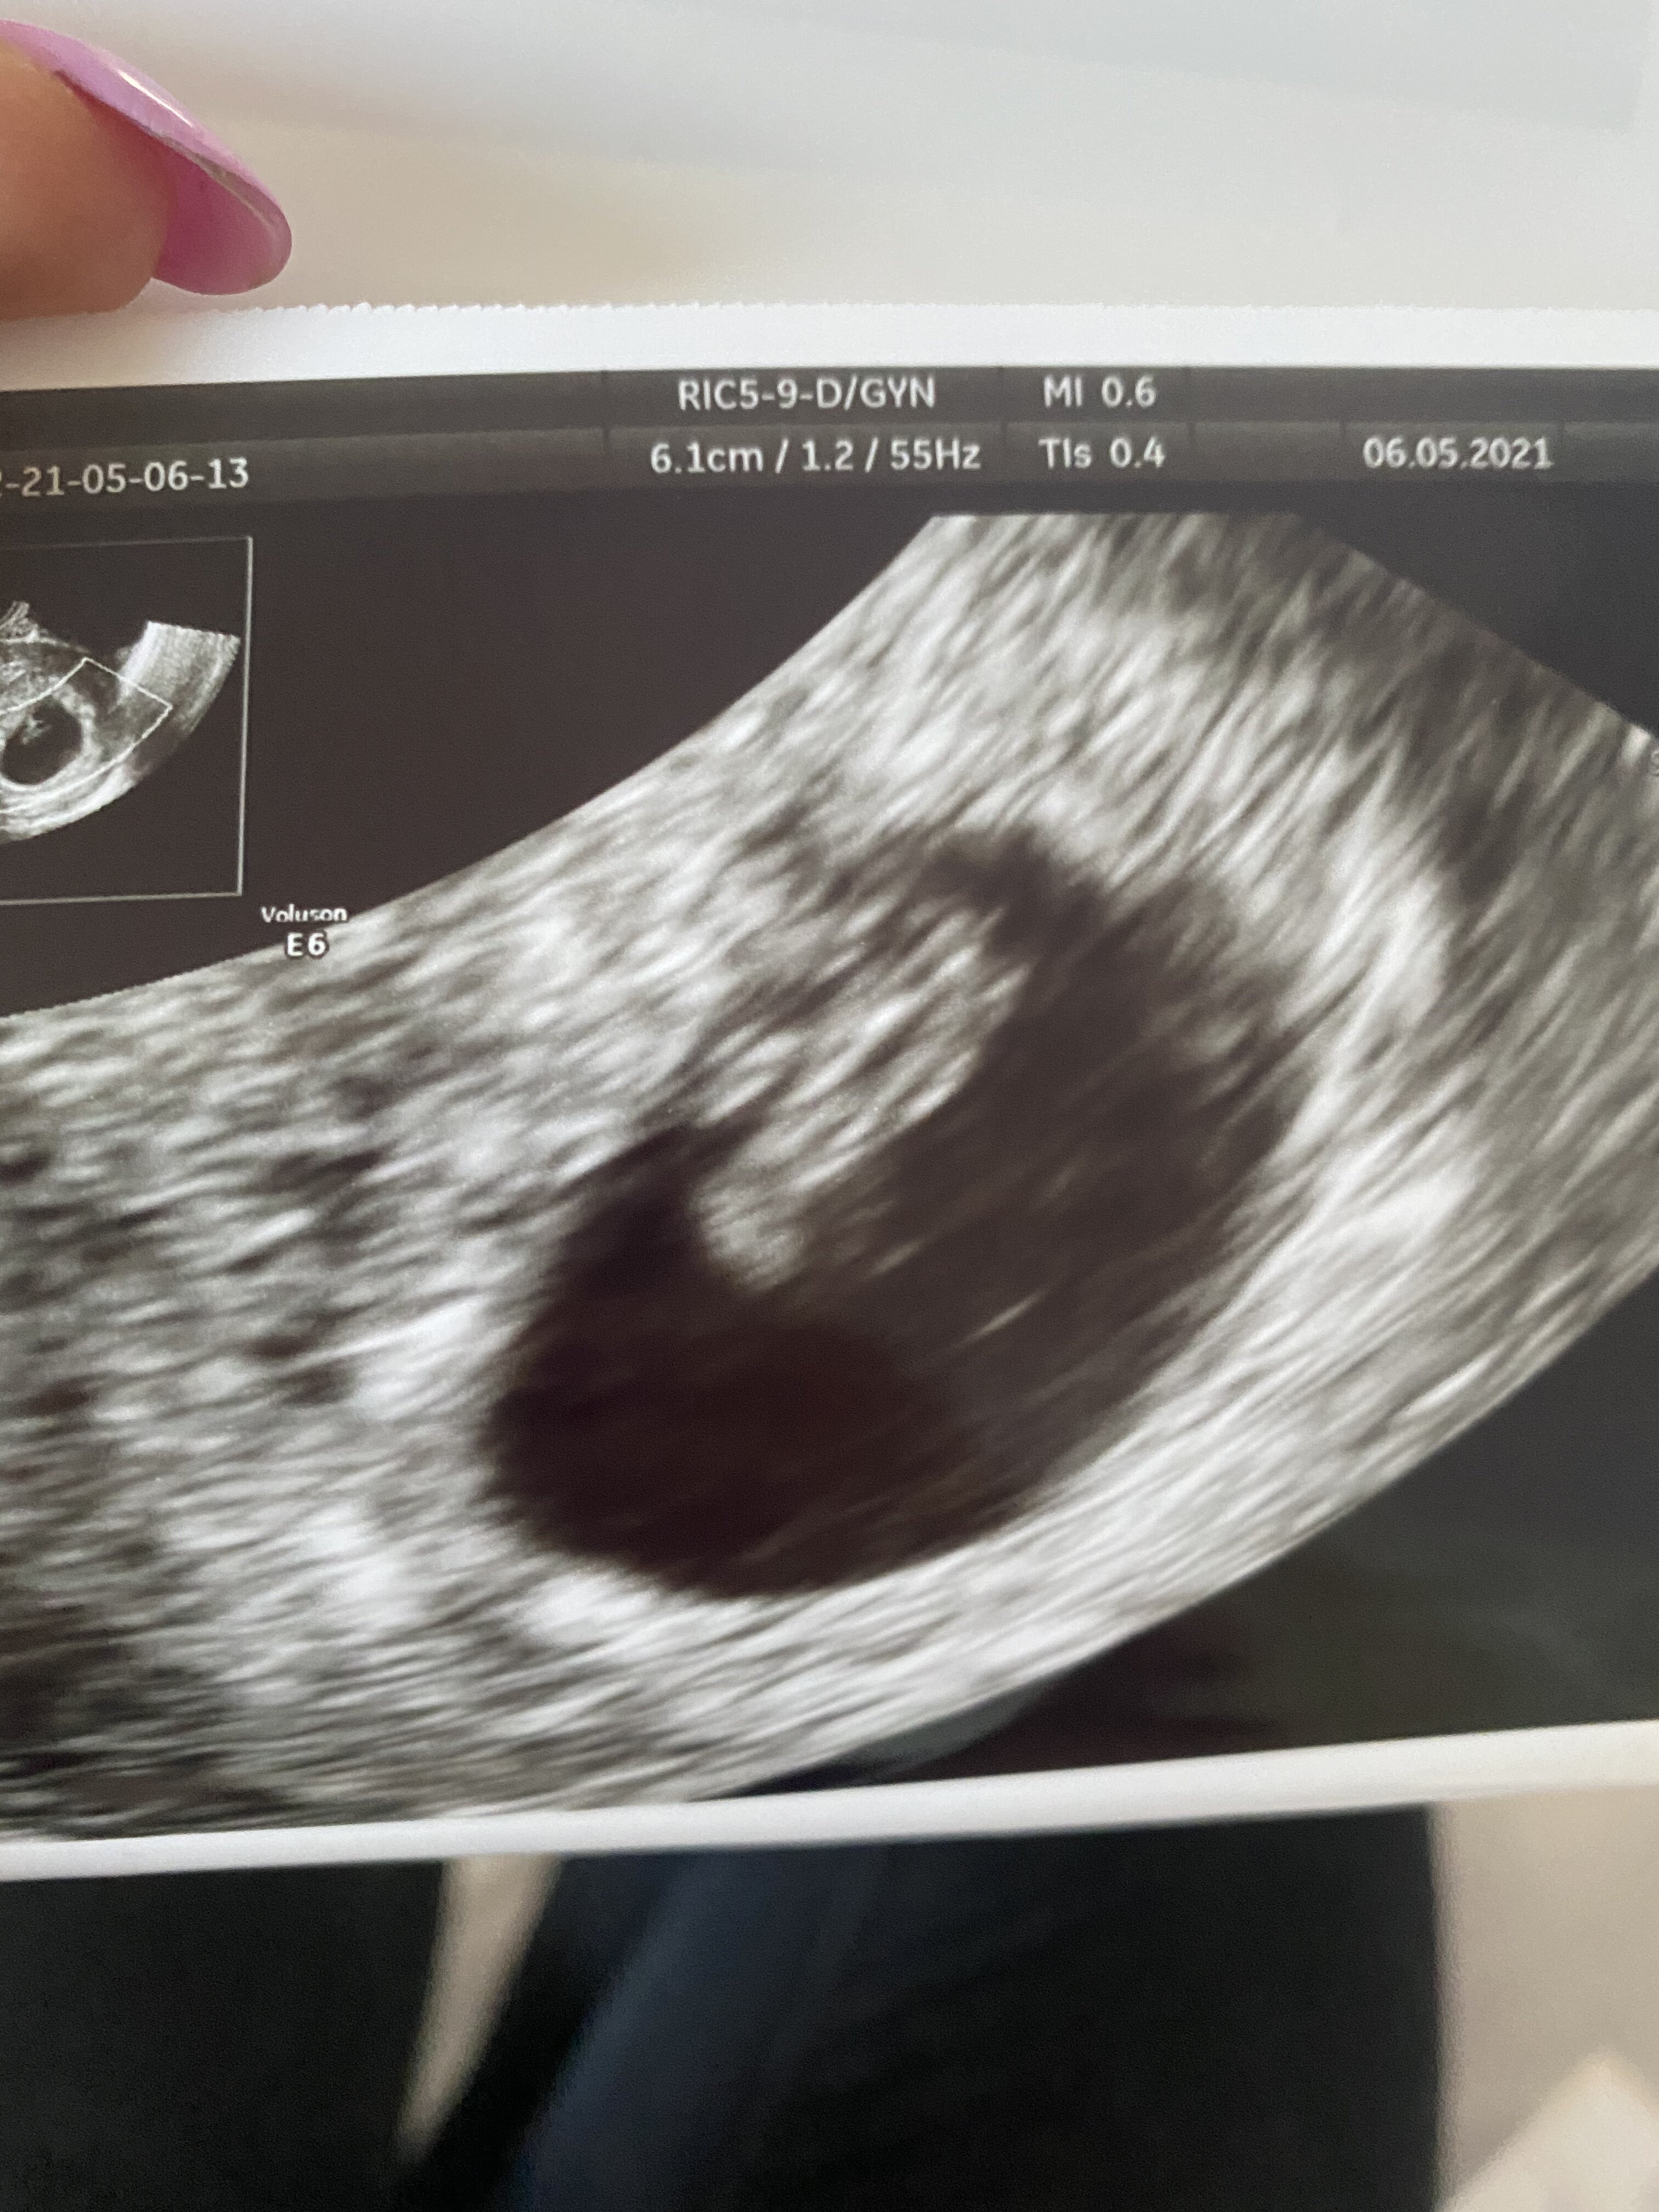

Uff byłam i wszystko ok

serducho bije, z usg 7+2, mam się nie stresować, objawy mogły już mi minąć

mówi, ze wszystko już będzie dobrze bo to już duże dziecko, ma 1,14 cm